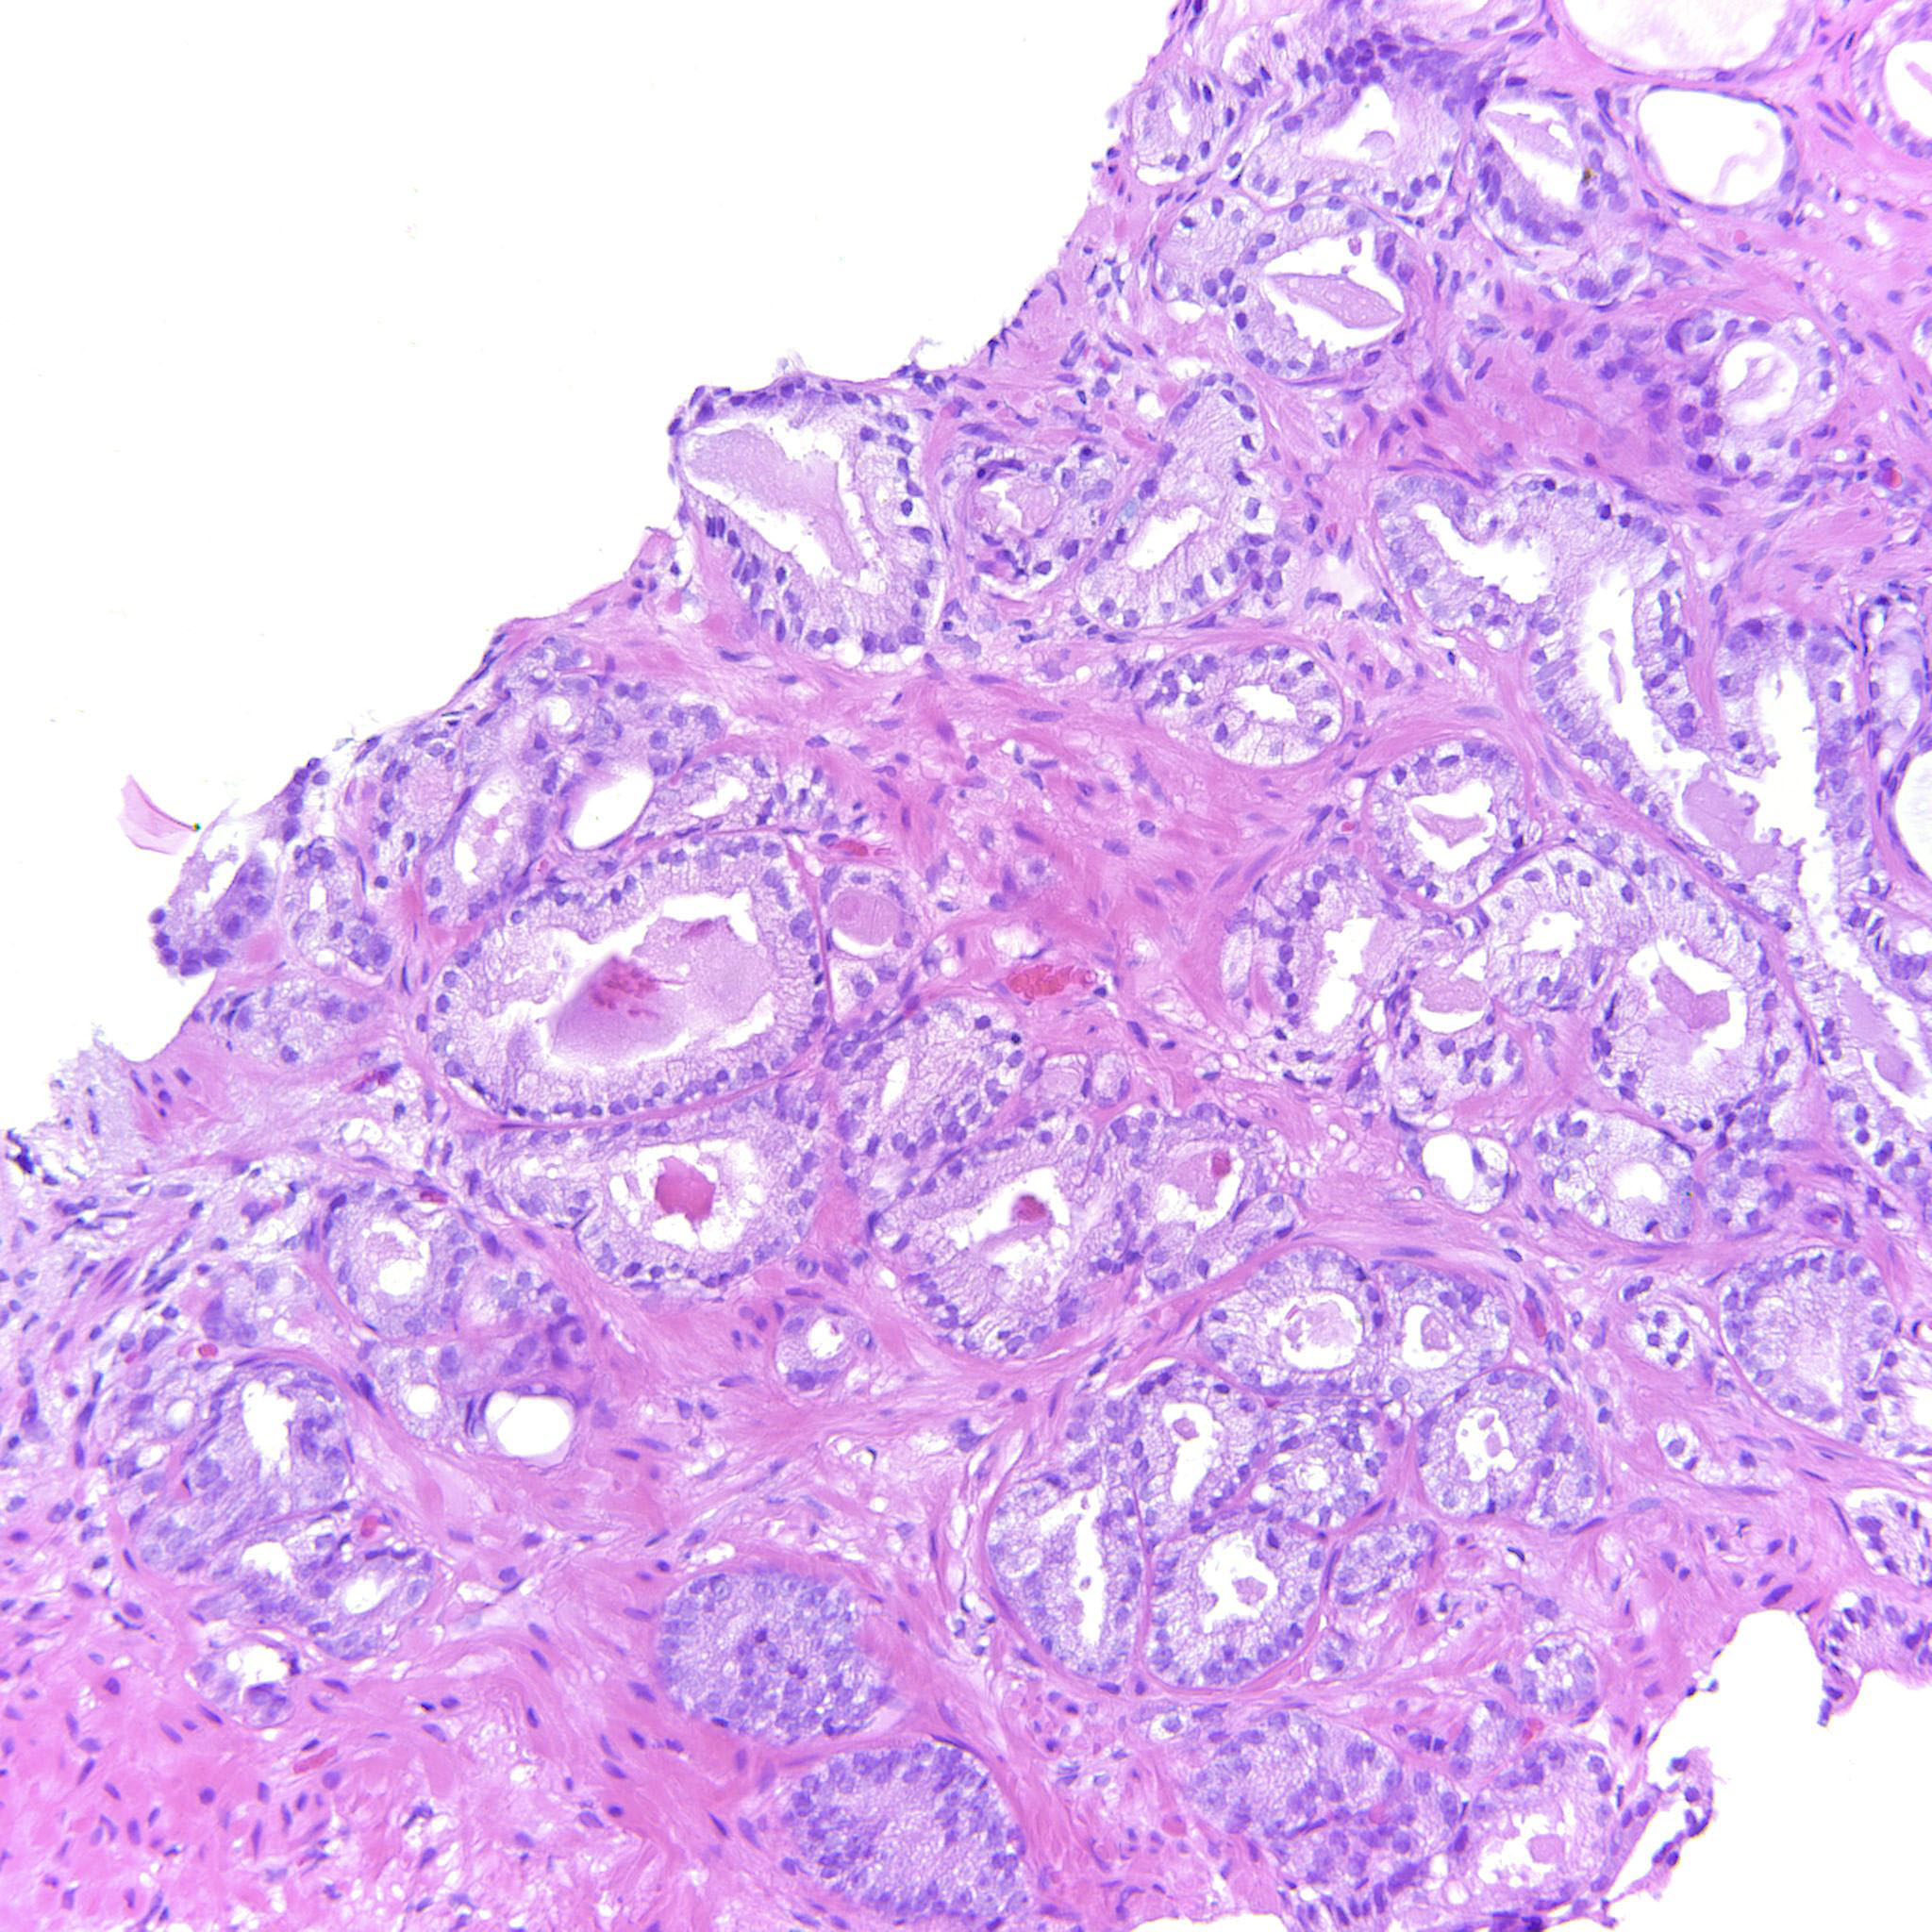

Prostate cancer grading

Case ID: 343